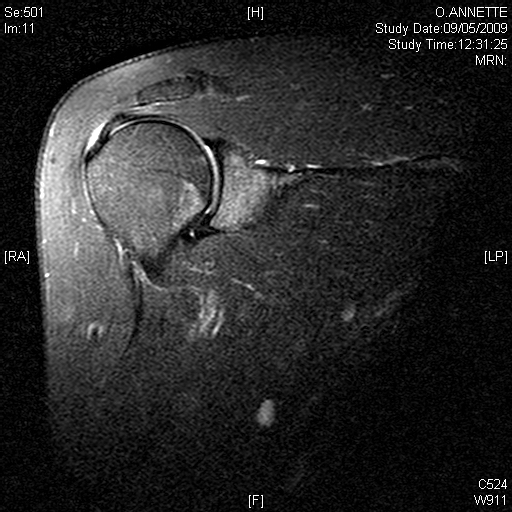

Deep to the deltoid run muscles from the shoulder blade attaching to the top of the humerus just at the edge of the joint. These muscles are known as the rotator cuff. They form a near continuous attachment to the bone so an injury to the tendon (the white sinewy part of the muscle that attaches to the bone) of one muscle often extends into its neighbouring rotator cuff muscle.

- The muscle over the top of the shoulder (Supraspinatus)

Deep to the rotator cuff lies the deepest layer of soft tissue, the joint capsule. The capsule is a thin but strong fibrous layer that is supple enough to allow full movement but strong enough to stop the shoulder dislocating. It is inflammation in the joint capsule which causes the capsule to stiffen reducing movement causing the symptoms of a frozen shoulder. At the opposite extreme tearing of the capsular attachment to bone is what allows shoulders to dislocate.

Beneath all these layers lie the cartilage covered bones of the shoulder joint formed by the humeral head (top of the humerus) and the glenoid (the oval joint surface of the scapula). Arthritis in the bones of the shoulder joint results in loss of the white shiny and smooth articular cartilage leaving the much rougher bones directly in contact with each other.